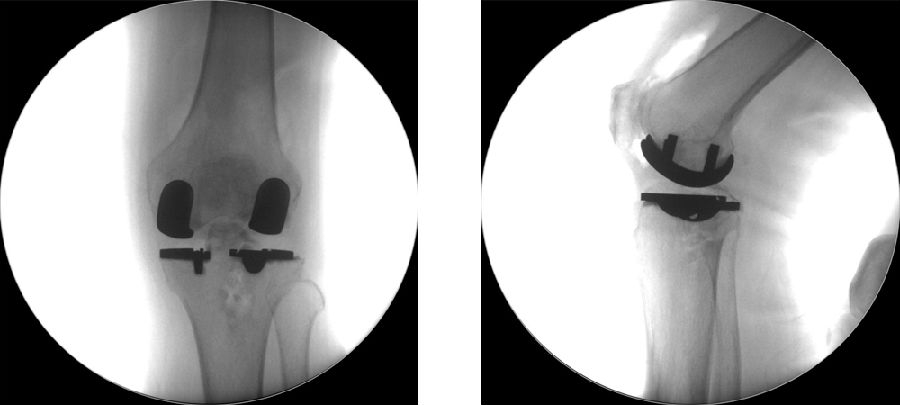

术后

术后透视。A.正位B.侧位